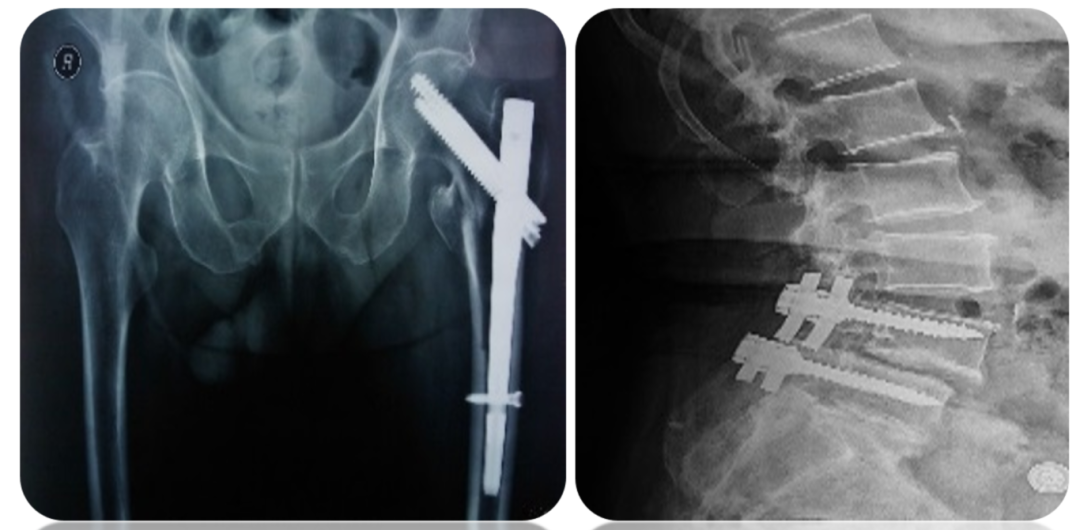

骨质疏松最严重的后果就是伴发的骨折,常见部位包括髋部、脊柱和手腕等。髋部骨折尤其危险,经常被称为是“人生最后一次骨折”,致残率和死亡率都很高。此外,骨质疏松还会导致疼痛、驼背、身高变矮等问题,严重影响生活质量。